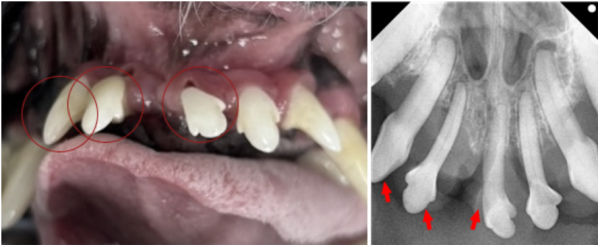

​[치아·잇몸 상태 점검 GBR/GTR(치조골 재생술) 전 점검]

de70cef8385ff32e9ecfc65bf523daeb_1766380418_7505.png

상악 앞니 주변에서 치조골 소실이 확인되며

잇몸과 치아 사이 공간이 생긴 것이 문제의 시작이었습니다.

방사선 검사 결과, 201·102·103번 치아는

치조골 손실이 심해 발치 후 봉합 치료가 필요했습니다.

이 부위의 치아는 흔들림도 있었고

강아지 치아를 지지하는 구조가 많이 약화된 상태였습니다.